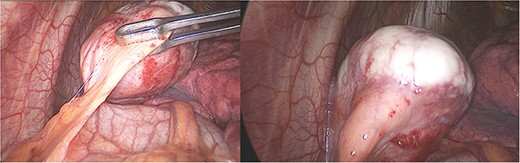

Pathology reported a 38 × 29 × 28 mm smooth tumor. It had a grayish external surface, few cystic areas and yellowish serous contents. The microscopic report revealed a well-defined tumor, surrounded by a thickened fibrous connective capsule with focal areas of calcification without invasion and numerous small CD5-positive lymphocytes (Fig. 3). B2 Thymoma in the mediastinum was the final diagnosis.

(a) Well-defined tumor formation, surrounded by a thickened fibrous connective capsule with focal areas of calcification and numerous small CD5-positive lymphocytes. (b) Immunohistochemistry shows a proliferative index of 30% with isolated positivity for CD20-positive B lymphocytes.